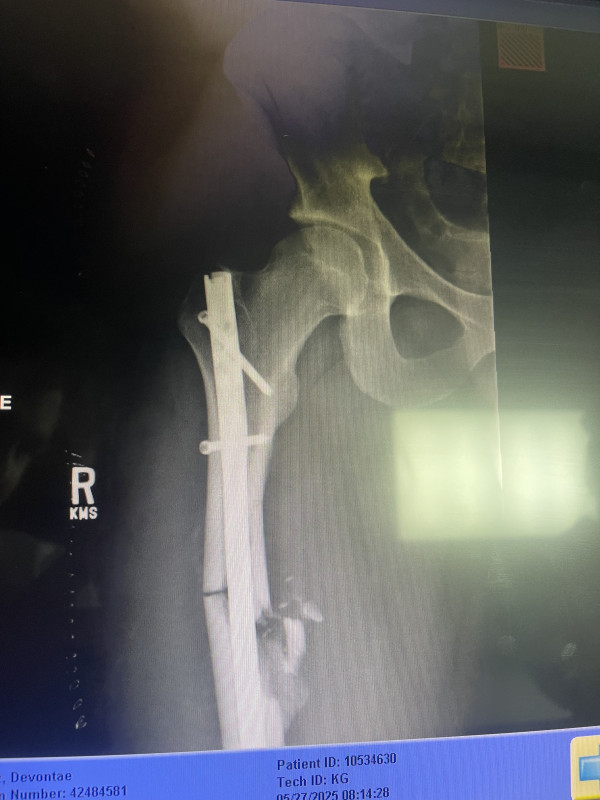

Hello, my son was in a motorcycle accident and broke his femur. Thankfully he was wearing his helmet or this would be a totally different situation. He is a young man so recovery is hopeful with many many months of physical therapy. The healing process for a broken femur is not a quick one. He will be unable to work for quite awhile. Medical bills and physical therapy help would be much appreciated. Thank you for your time.